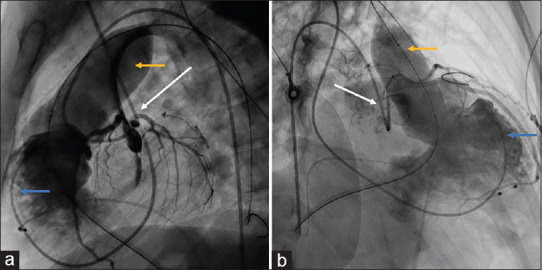

Transcatheter pulmonary valve implantation (TPVI) is the standard of care in patients with repaired tetralogy of Fallot (rTOF) presenting with right ventricular outflow tract (RVOT) dysfunction. However, the feasibility of TPVI is limited by the high cost and nonavailability of larger-sized valves for dilated native RVOT of rTOF patients. We report the first successful TPVI with a custom-made 35 mm balloon-expandable valve (Myval™) in a 30-year-old rTOF patient with severe pulmonary regurgitation and RV dysfunction.

Abstract Image